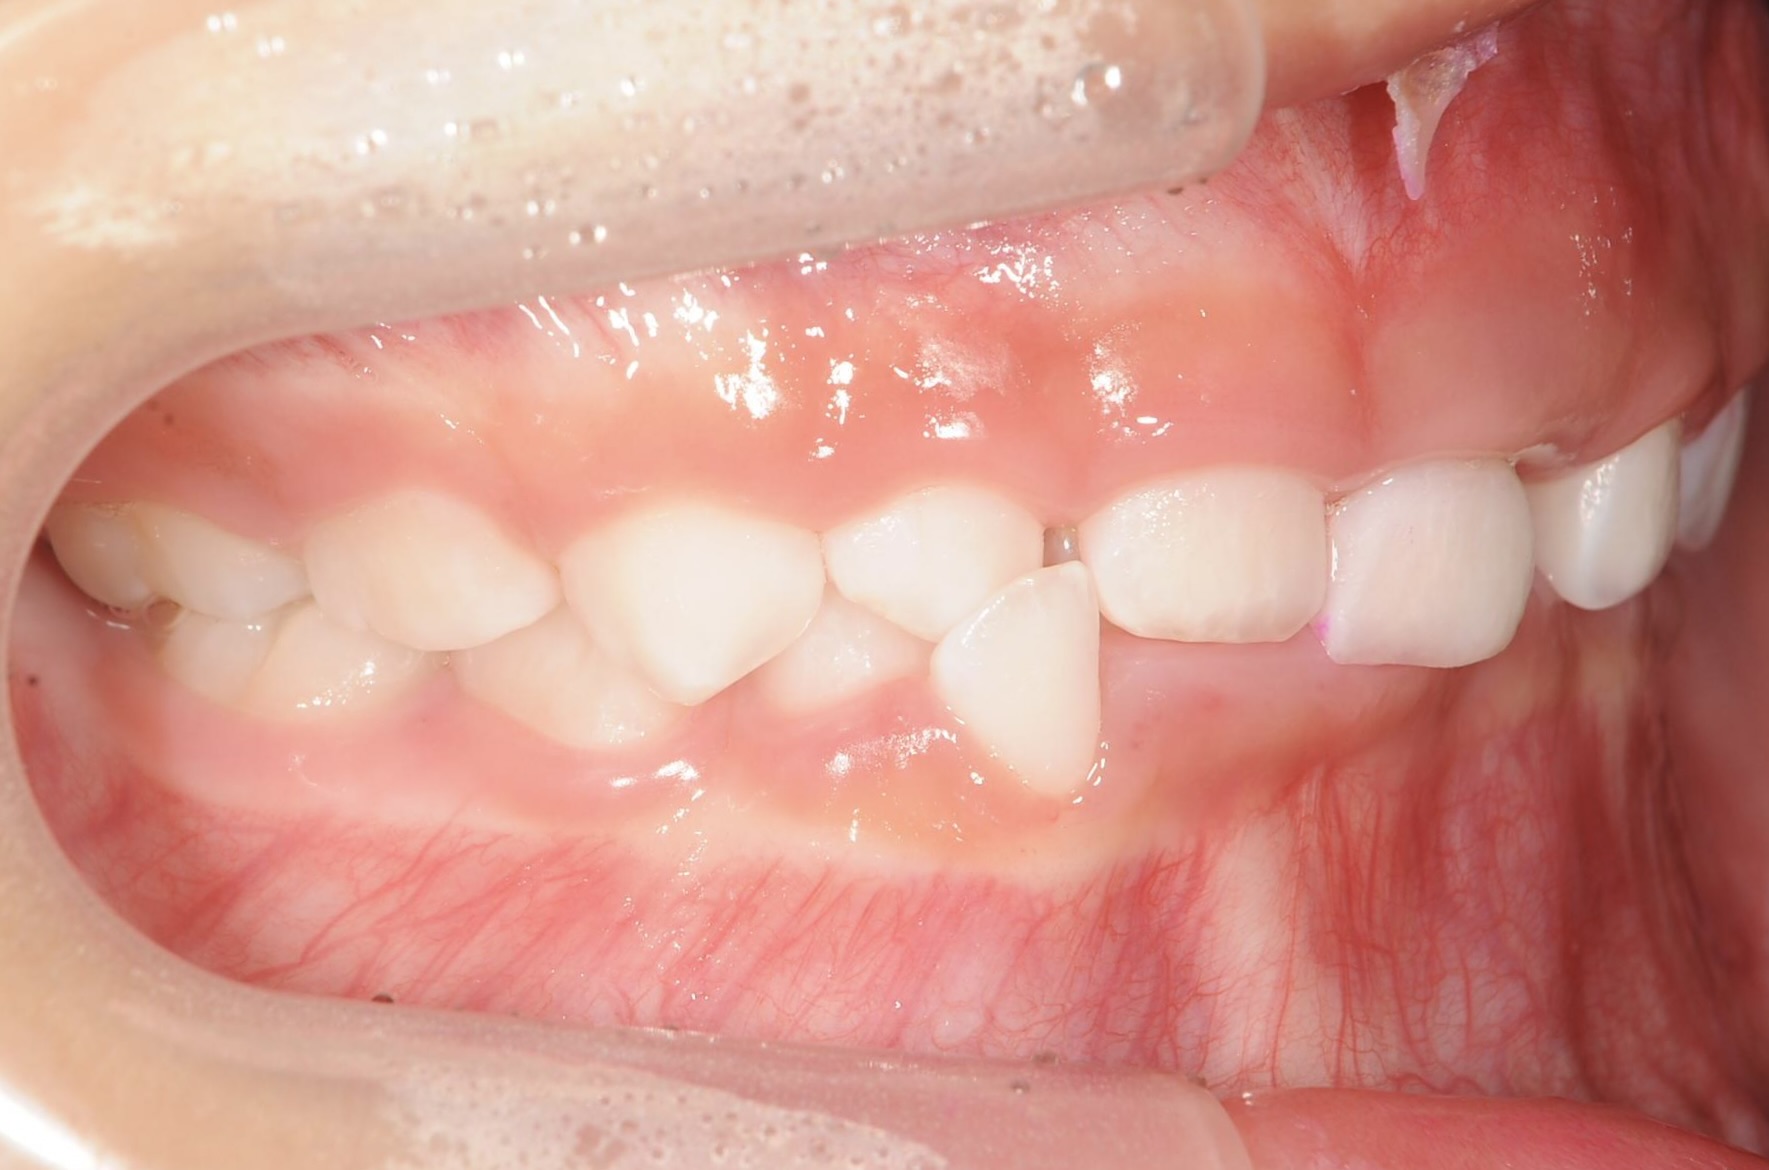

5歳 女児 小児矯正

歯並びの状態:

叢生(ガタガタ)

過蓋咬合(咬み合わせが深い)

BEFORE

AFTER

主訴

右下の歯が飛び出ているので治したい。

診断名・主な症状

過蓋咬合

治療内容

上下の歯並びの幅を拡げつつ、前歯の関係を改善しました。

治療期間

2年 + 後戻り止め期間(5年)

通院回数

25回

費用

50万円程度(税別)